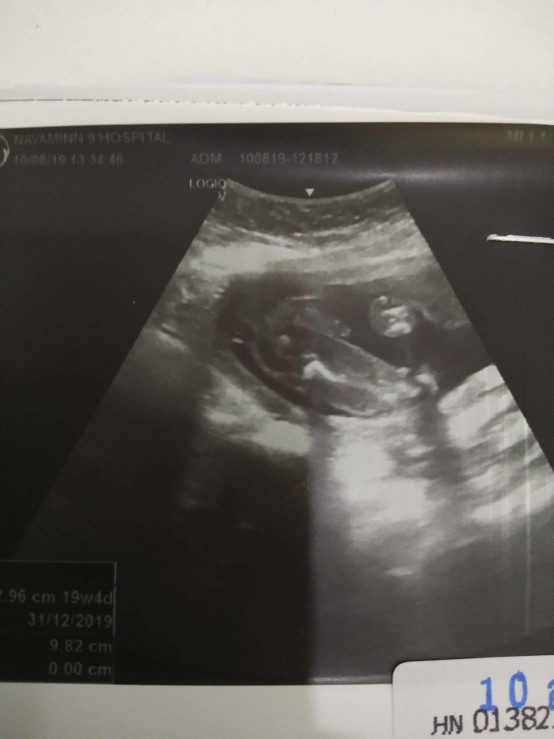

โชว์ผลซาวด์กันค่ะ

คุณลุงหมอบอกมีกลีบ?ใครมีกลีบ ใครมีแท่ง ลงมาอวดกันจร้า

บ้านนี้ยังไม่แน่ใจคะ ว่า ญช

จู๋ชัดมากค่ะ..5เดือนแล้ว

คลอดบุตร